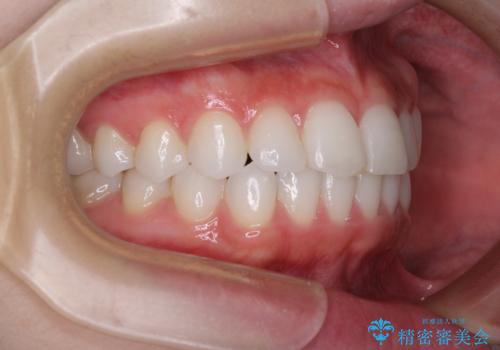

矯正治療は8ヶ月ほどで終了し、速やかに虫歯治療に移行することができました。

保険治療で用いる樹脂(コンポジットレジン)で行った虫歯治療は、周辺が変色して汚くなっていましたが、下顎はセラミックインレーで審美的に、上顎はPGAインレーで歯に負担の少ない治療を行うことができました。